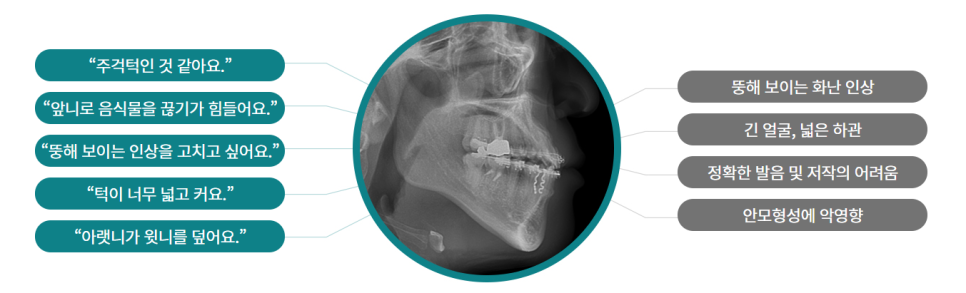

주걱턱(반대교합)이라면..?

정상적인 교합은 윗니가 아랫니를 살짝 덮는 것인데 주걱턱의 경우

윗니보다 아랫니가 나와있어 앞니로 음식물을 끊기 어렵습니다.

또 대부분은 긴 얼굴, 넓은 하관으로 형성되어 콤플렉스가 되기 쉽습니다.

주걱턱이라고 해서 원인이 다 같은 것은 아닌데요

턱이 너무 넓거나 큰 경우도 있고 반대로 윗 턱이 좁은 경우도 있습니다.